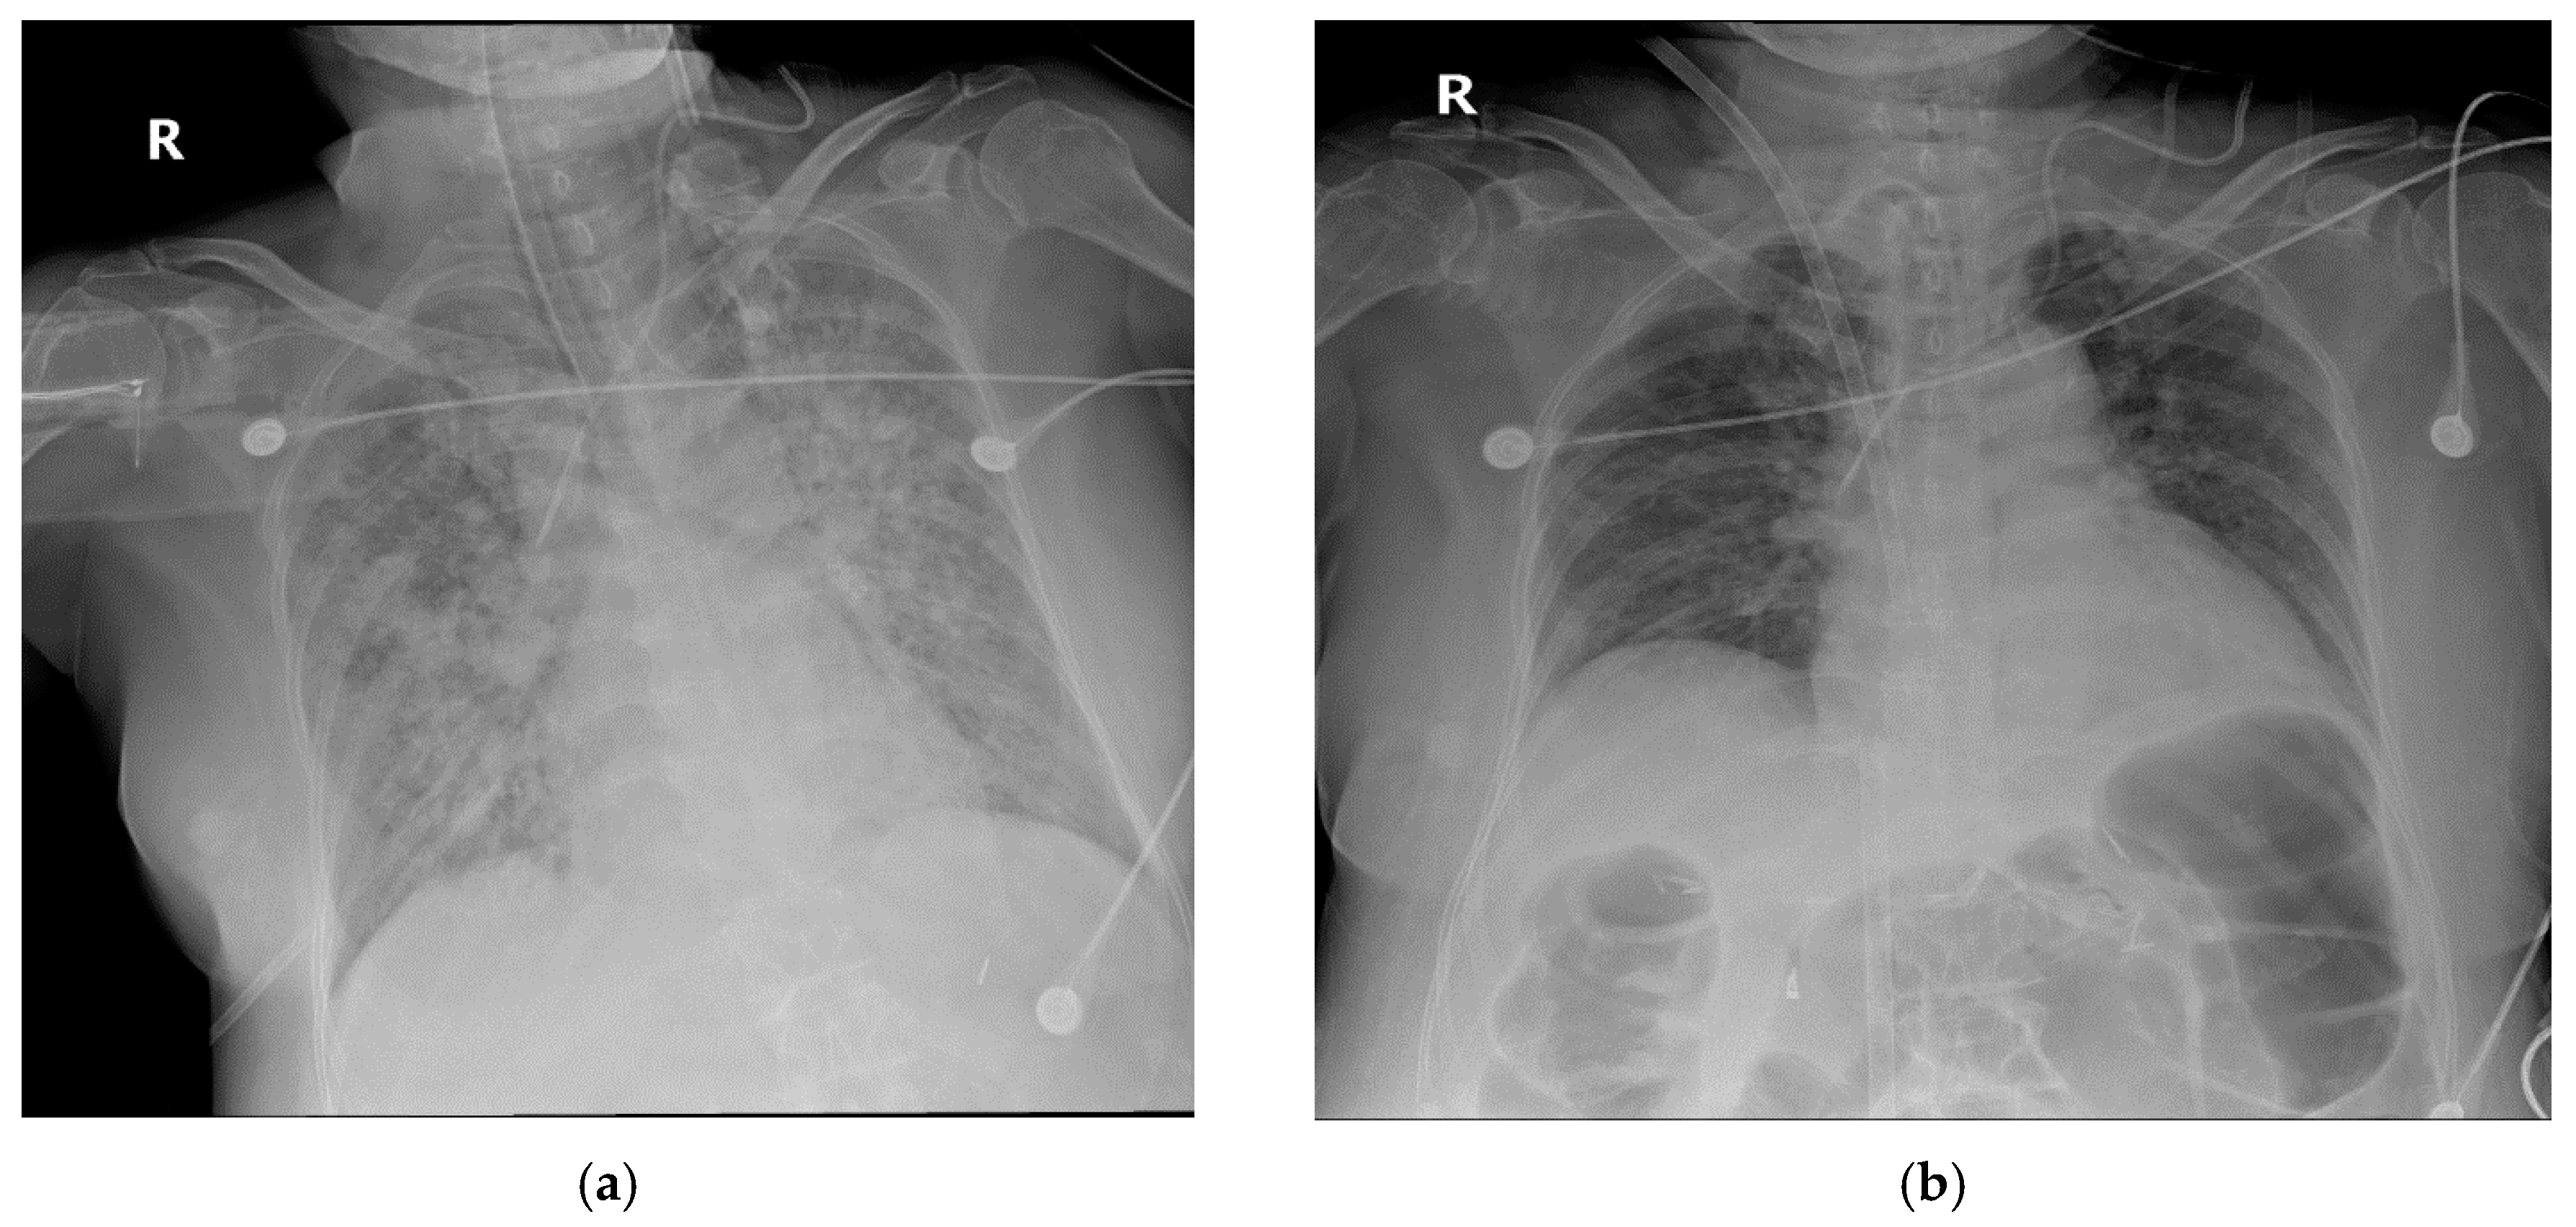

2.1. Case 1

2.2. Case 2